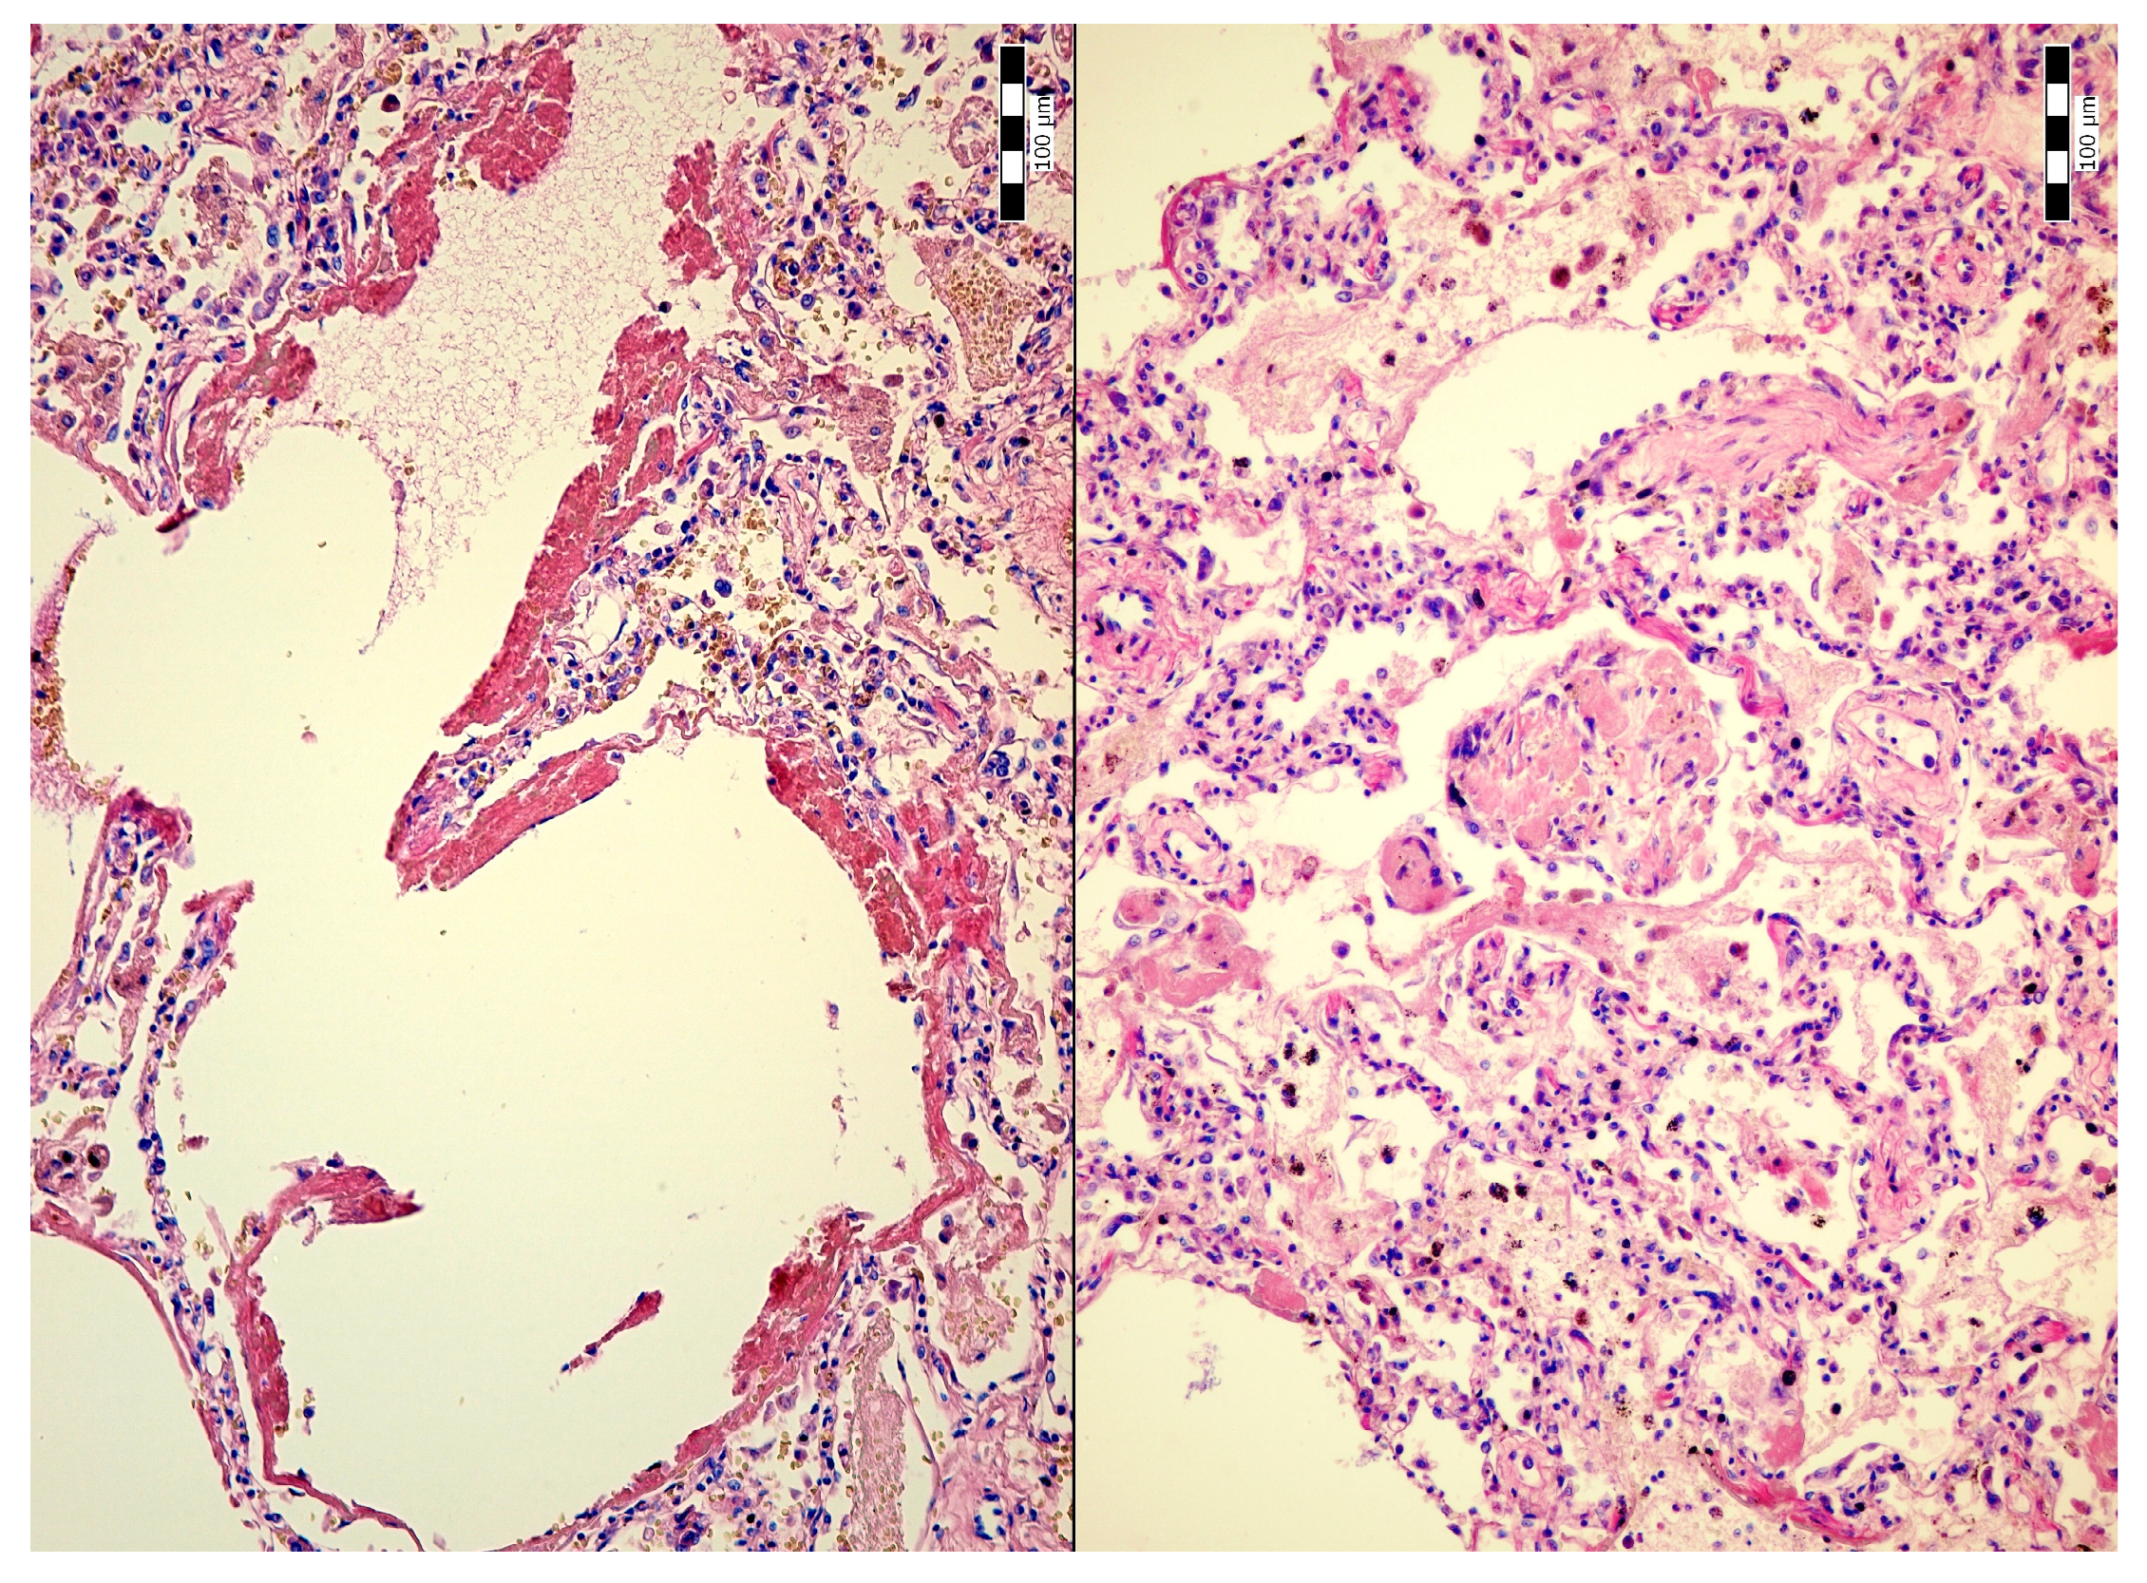

Alveolar Bile and Light Chain Immunoglobulin Depositions as an Unusual Complication of Transjugular Liver Biopsy Resulting in Bilhemia in a Patient with Multiple Myeloma

2. Case Description